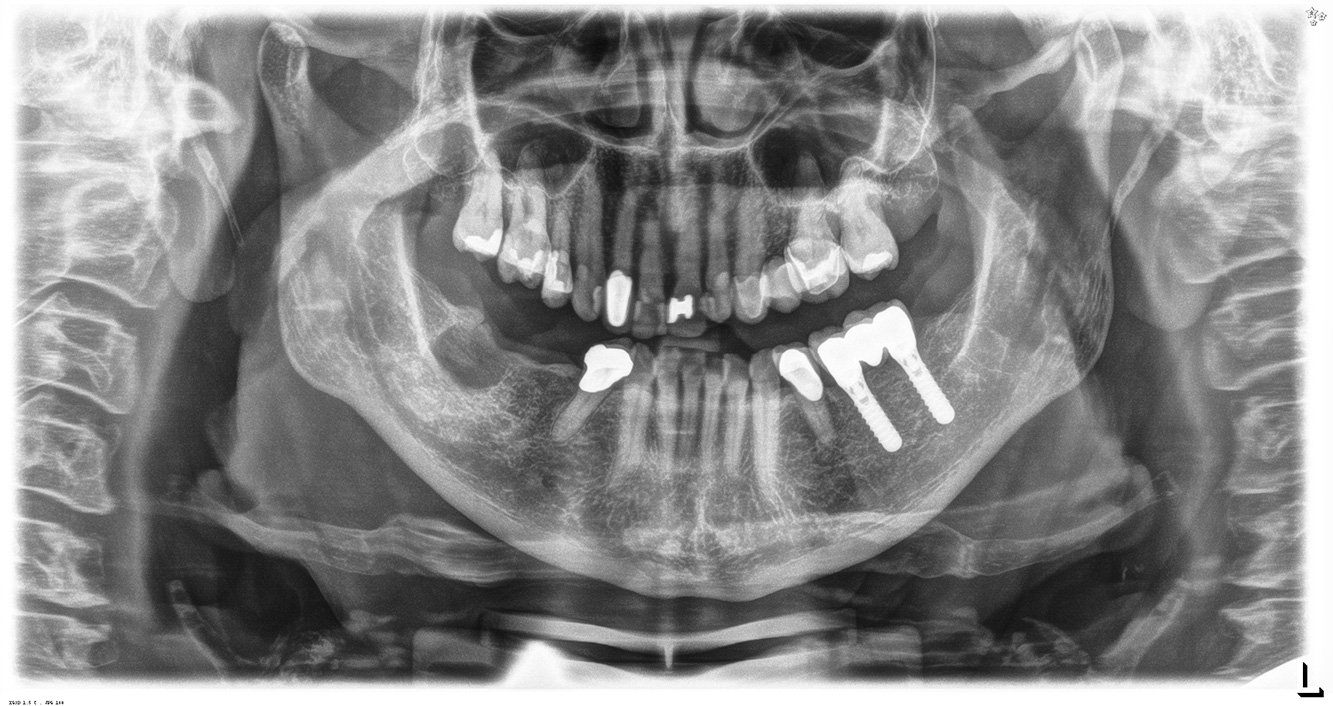

Die 68-jährige Patientin hat keine zahnmedizinisch relevanten allgemeingesundheitlichen Vorerkrankungen oder Medikation, auch aus dem Lebensstil ergibt sich kein besonderes Risiko. Die Patientin hat zwei Implantate (3. Quadrant, seit fünf Jahren) sowie eine parodontale Vorerkrankung (Parodontitis Stadium IV, Grad B) mit Zahnverlust. Derzeit zeigen sich stabile parodontale Verhältnisse. Für die Prophylaxesitzung ergeben sich vier Empfehlungen in den Bereichen Anamnese/Befund, Motivation/Instruktion, der Wahl der geeigneten Instrumente und für Resümee/Folgetermin.

Da die Patientin keine besonderen Risikofaktoren mit spezifischen zahnmedizinischen Auswirkungen hat, ist der aus der Mundgesundheit ermittelte Bedarf maßgebend. Hier ist einmal jährlich ein ausführlicher Parodontalstatus empfohlen. So kann rechtzeitig auf eine mögliche Progression der parodontalen Vorerkrankung oder die Entstehung einer Periimplantitis reagiert werden.

In der Instrumentierung gilt im Bereich der Implantate eine besondere Vorgehensweise. Zum Erhalt der Implantatoberfläche bei gleichzeitig effektiver Reinigung ist die Wahl passender Pulver und Instrumente ausschlaggebend, wie etwa der gezielte Einsatz von Pulverstrahlgeräten mit speziellen Paro-Spitzen. Die Wahl des geeigneten Pulvers kann bedarfs- und risikogerecht erfolgen, beispielsweise kann neben dem passenden Abrasionsgrad auch auf diätische Anforderungen (u. a. zuckerfrei, salzarm) eingegangen werden.

Aufgrund der Implantatsituation mit parodontaler Vorerkrankung hat die Patientin ein Entstehungsrisiko für eine Periimplantitis – empfohlen wird eine Wiedervorstellung im Intervall von drei bis vier Monaten.